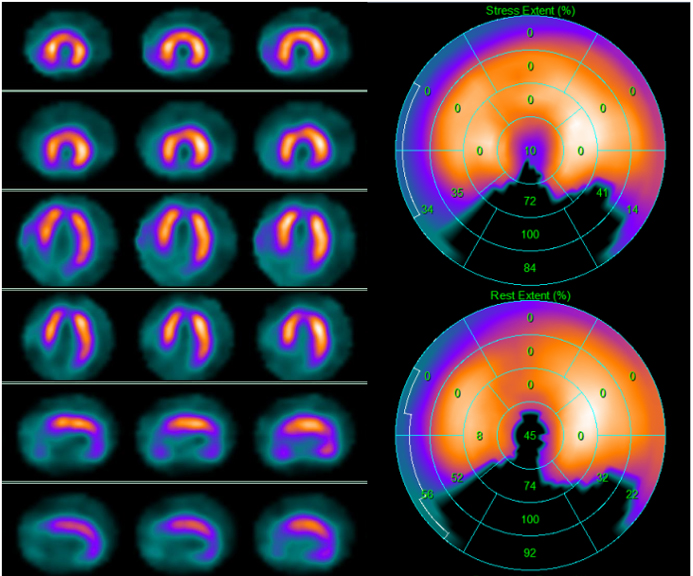

Fig. 3.99mTc-tetrofosmin cardiac single photon emission computed tomography (SPECT) images in a 74-year-old woman with arterial hypertension, diabetes mellitus, and a history of obstructive CAD without myocardial infarction treated with triple coronary artery bypass surgery five years earlier. Perfusion imaging was ordered to assess ischemia due to persistent atypical angina after medical therapy optimization. SPECT revealed a large reversible defect in the anterior and the lateral walls showing severe myocardial ischemia. Subsequent angiography revealed complete occlusion of the left main artery, occlusion of the saphenous vein graft anastomosed to the diagonal branch of the left anterior descendent coronary artery, and patency of the other two bypass grafts. Medical therapy was optimized. Left side top row: stress-rest short axis; stress-rest horizontal long axis; stress-rest vertical long axis; right side: polar map of stress (upper image) and rest perfusion (lower image).